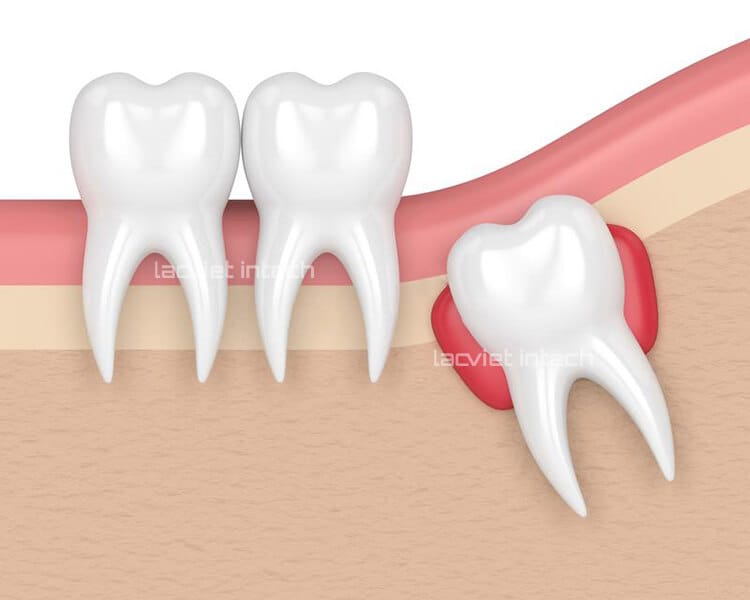

Ngoài ra, một số trường hợp răng khôn mọc ngầm dưới nướu còn gây viêm lợi, đau nhức hay mọc lệch, mâm ngang… Điều này sẽ khiến răng kế cận bị tổn thương, dễ gây mất răng nếu không được khắc phục kịp thời.